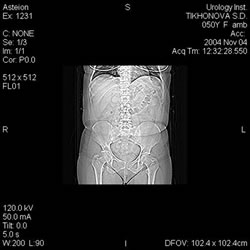

Компьютерная

томография: |

|